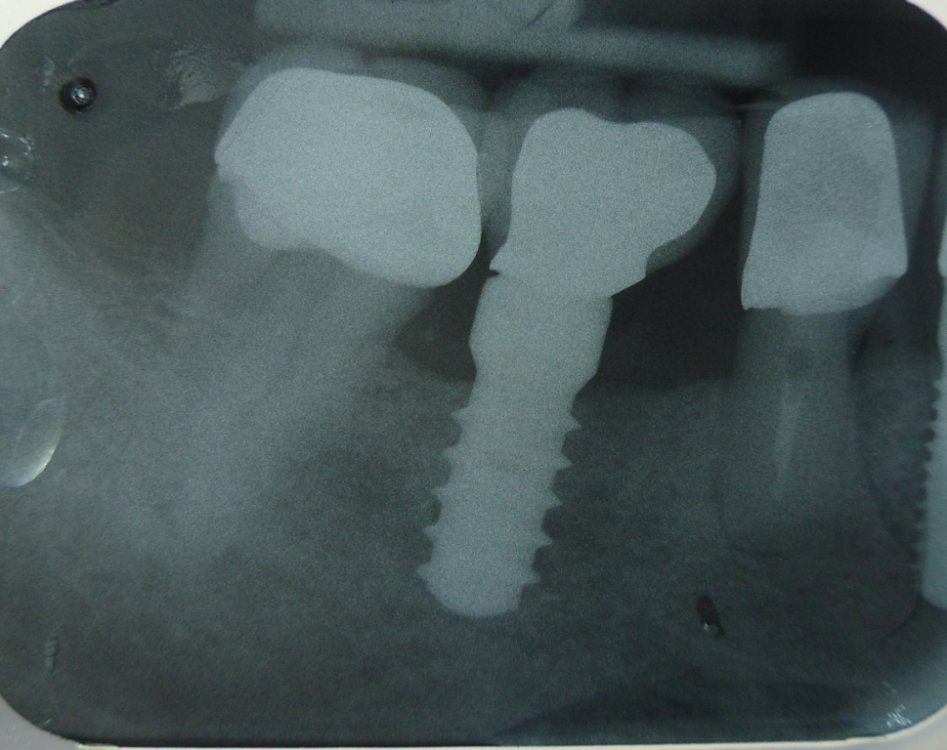

Al primo FU si rilevano i valori di BoP, PI e PPD e si prendono RX periapicali.

L' igiene orale del paziente, nonostante le sue oggettive limitazioni manuali, e' al momento soddisfacente e dovra' essere mantenuta nel tempo